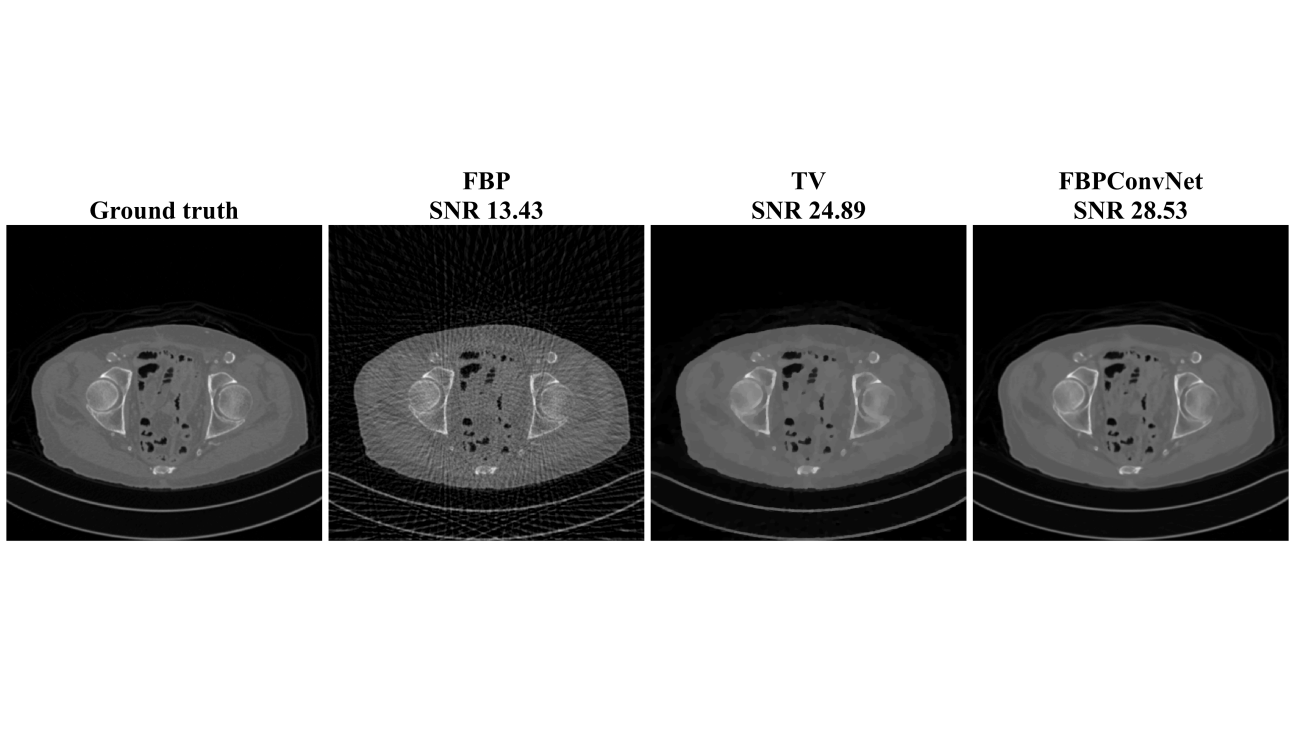

V-C Experimental Dataset

| FBP | TV [13] | Proposed | ||

| avg. SNR (dB) | 145 views (x5) | 5.38 | 8.25 | 11.34 |

| 51 views (x14) | 3.29 | 7.25 | 8.85 | |

Figures 7 and 8 and Table III show the results for the experimental dataset. The SNRs of all methods are significantly lower here because of the relatively low contrast of the sinogram. In Fig. 7, we observe the same trend as for the biomedical dataset, where the TV method oversmooths and the FBPConvNet better preserves fine structures. These trends also appears in twenty times downsampling case (x20) in Fig. 8. The FBPConvNet had a higher SNR than the TV method in both settings.